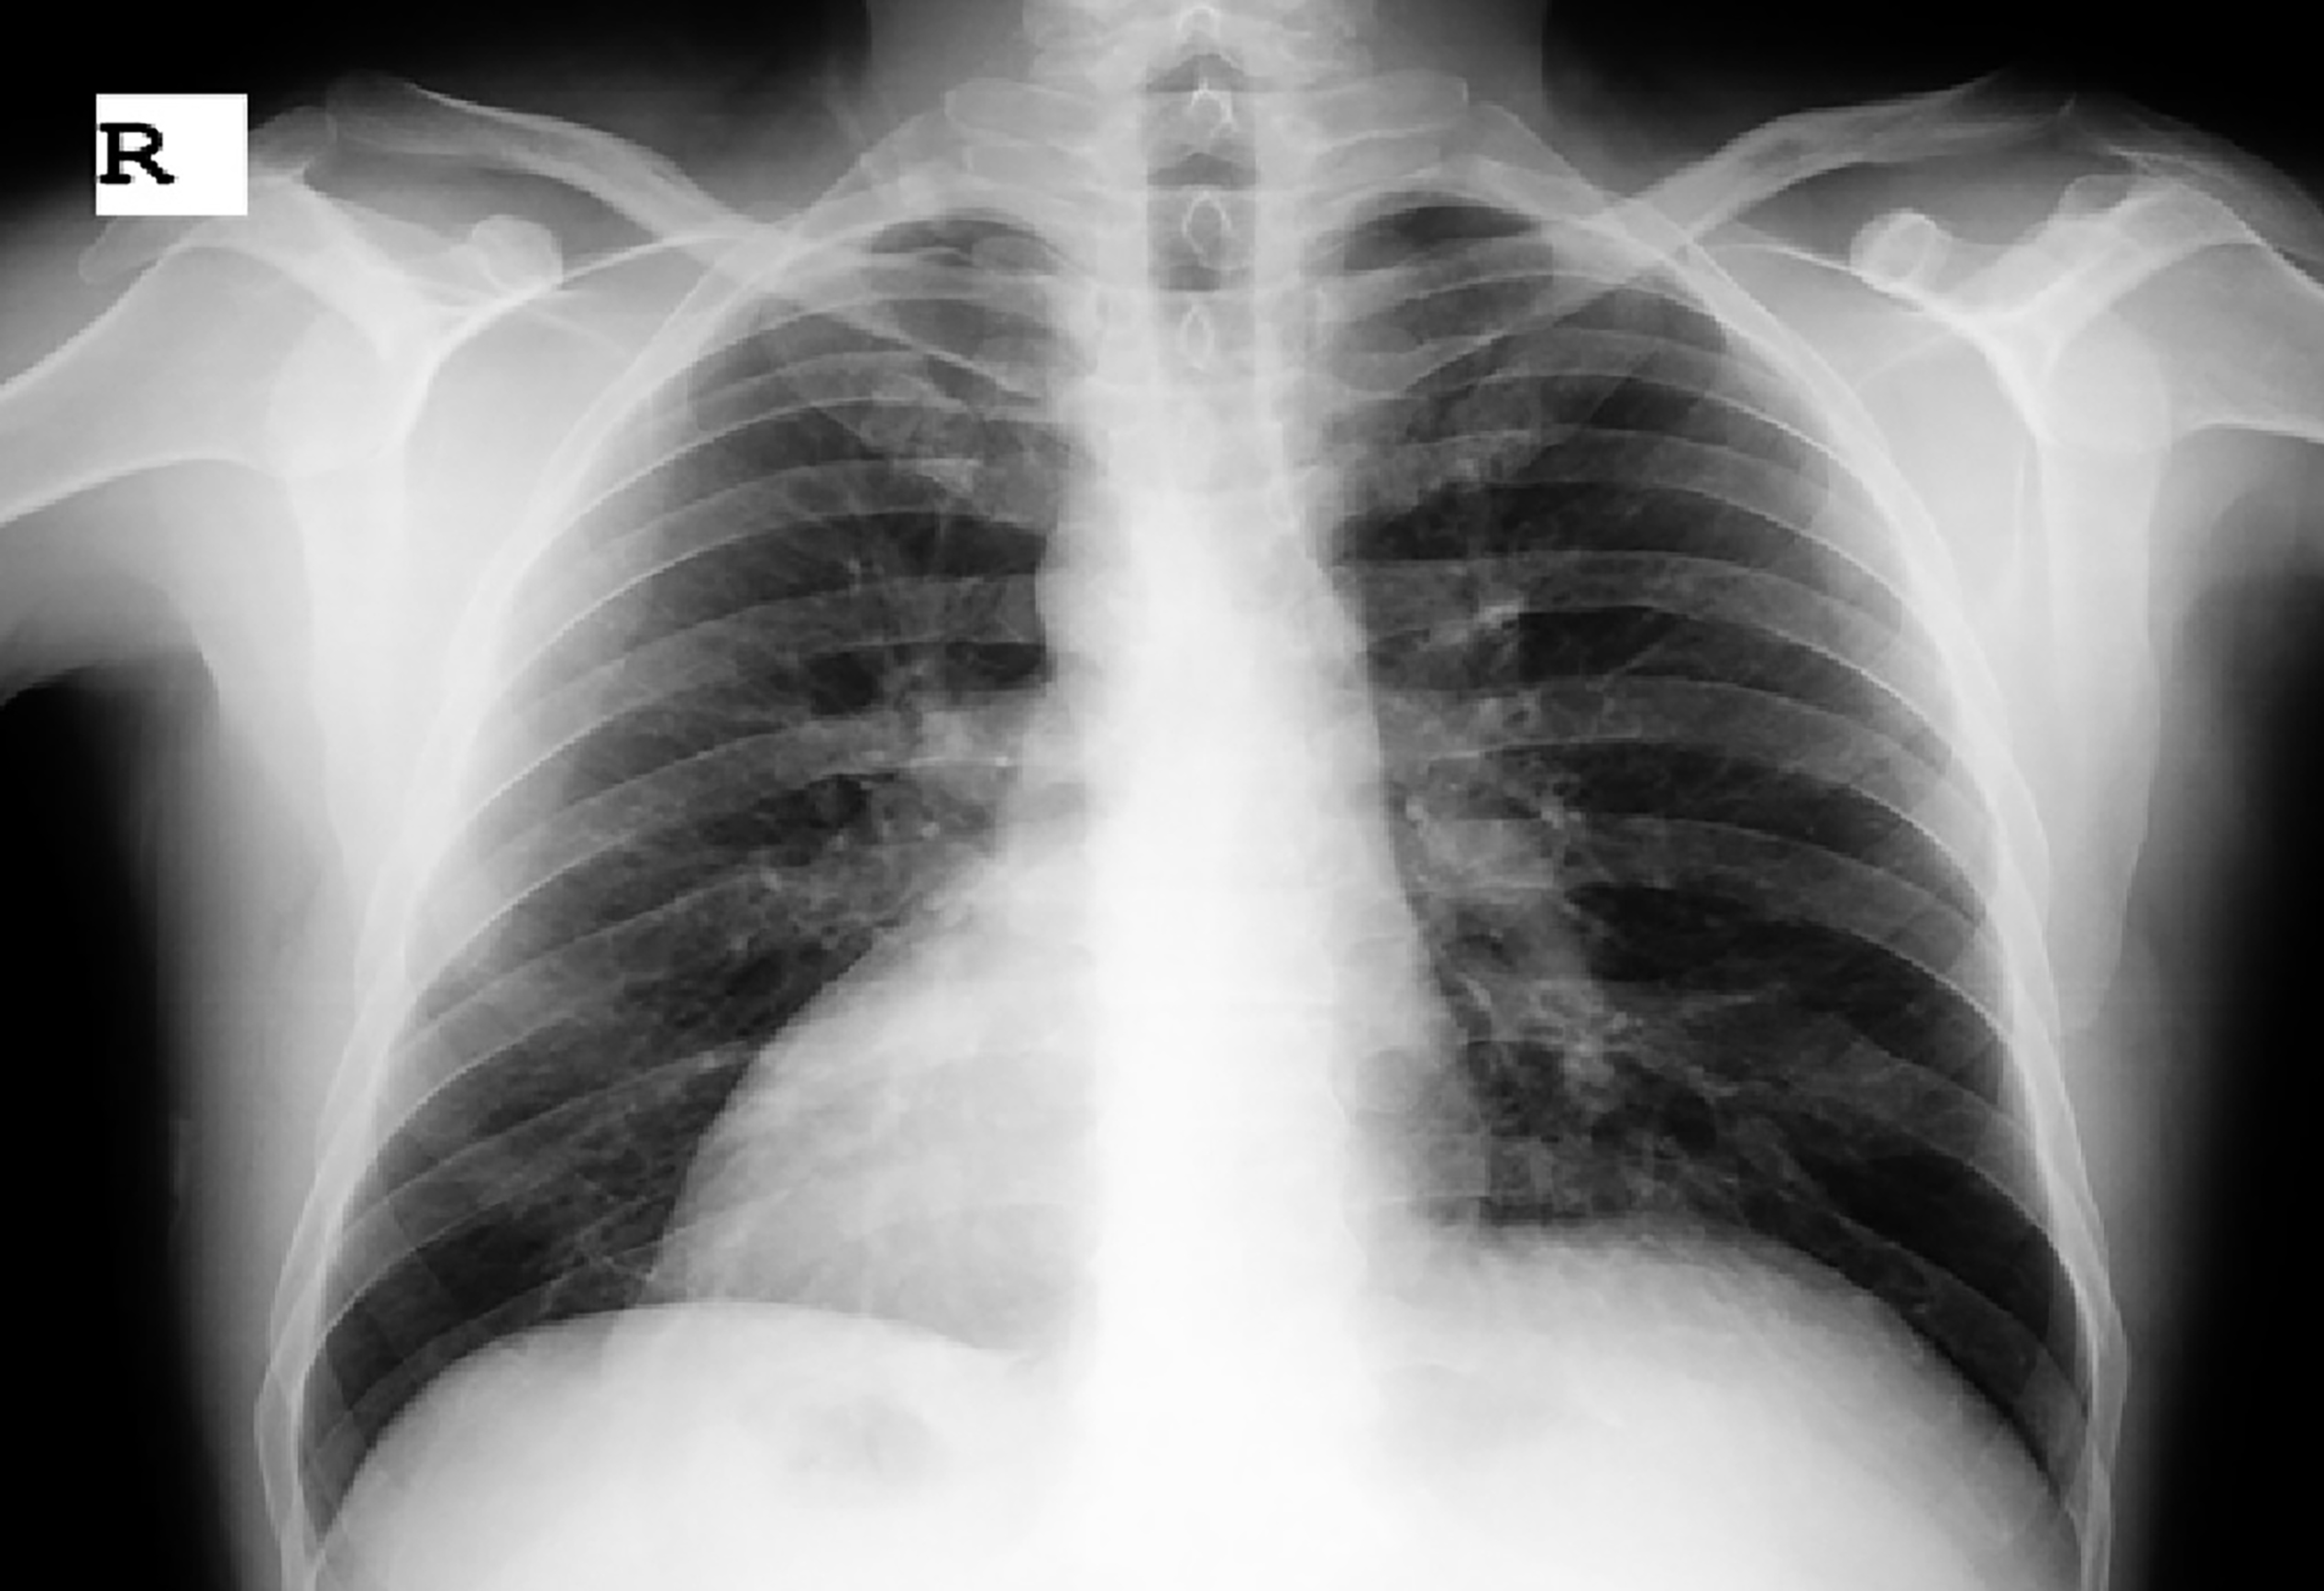

In cases with situs inversus totalis, if the person does not know this situation, as in our case, it will be difficult to diagnose appendicitis because the appendix is located in an abnormal location. The most important way to prevent complications that may occur is to make use of anamnesis, physical examination, and imaging tests. On physical examination, the heart crest is on the right, heart sounds are more pronounced on the right than on the left, and the liver is palpable on the left, suggesting SIT. The presence of dextrocardia and gastric fundus gas on the right side on direct radiographs is in favor of SIT (Figure 2).

Electrocardiographic findings are helpful in the diagnosis of dextrocardia. Computed tomography of the abdomen is useful in the differential diagnosis of intestinal malrotation and situs inversus totalis and has an accuracy rate of 90-98% in the diagnosis of acute appendicitis.8 In our case, it was thought that there might be diverticulitis at first, but when it was found out by tomography that it was situs inversus totalis, a diagnosis of acute appendicitis was made. The most common reason for surgical intervention in patients presenting with abdominal pain is acute appendicitis. It should be kept in mind that rare clinical conditions such as appendicitis may be present in patients with situs inversus totalis presenting with left lower quadrant pain. Early diagnosis is important as life-threatening complications may develop.

Figure 2

Figure 2. X-ray view of the heart and fundus gas